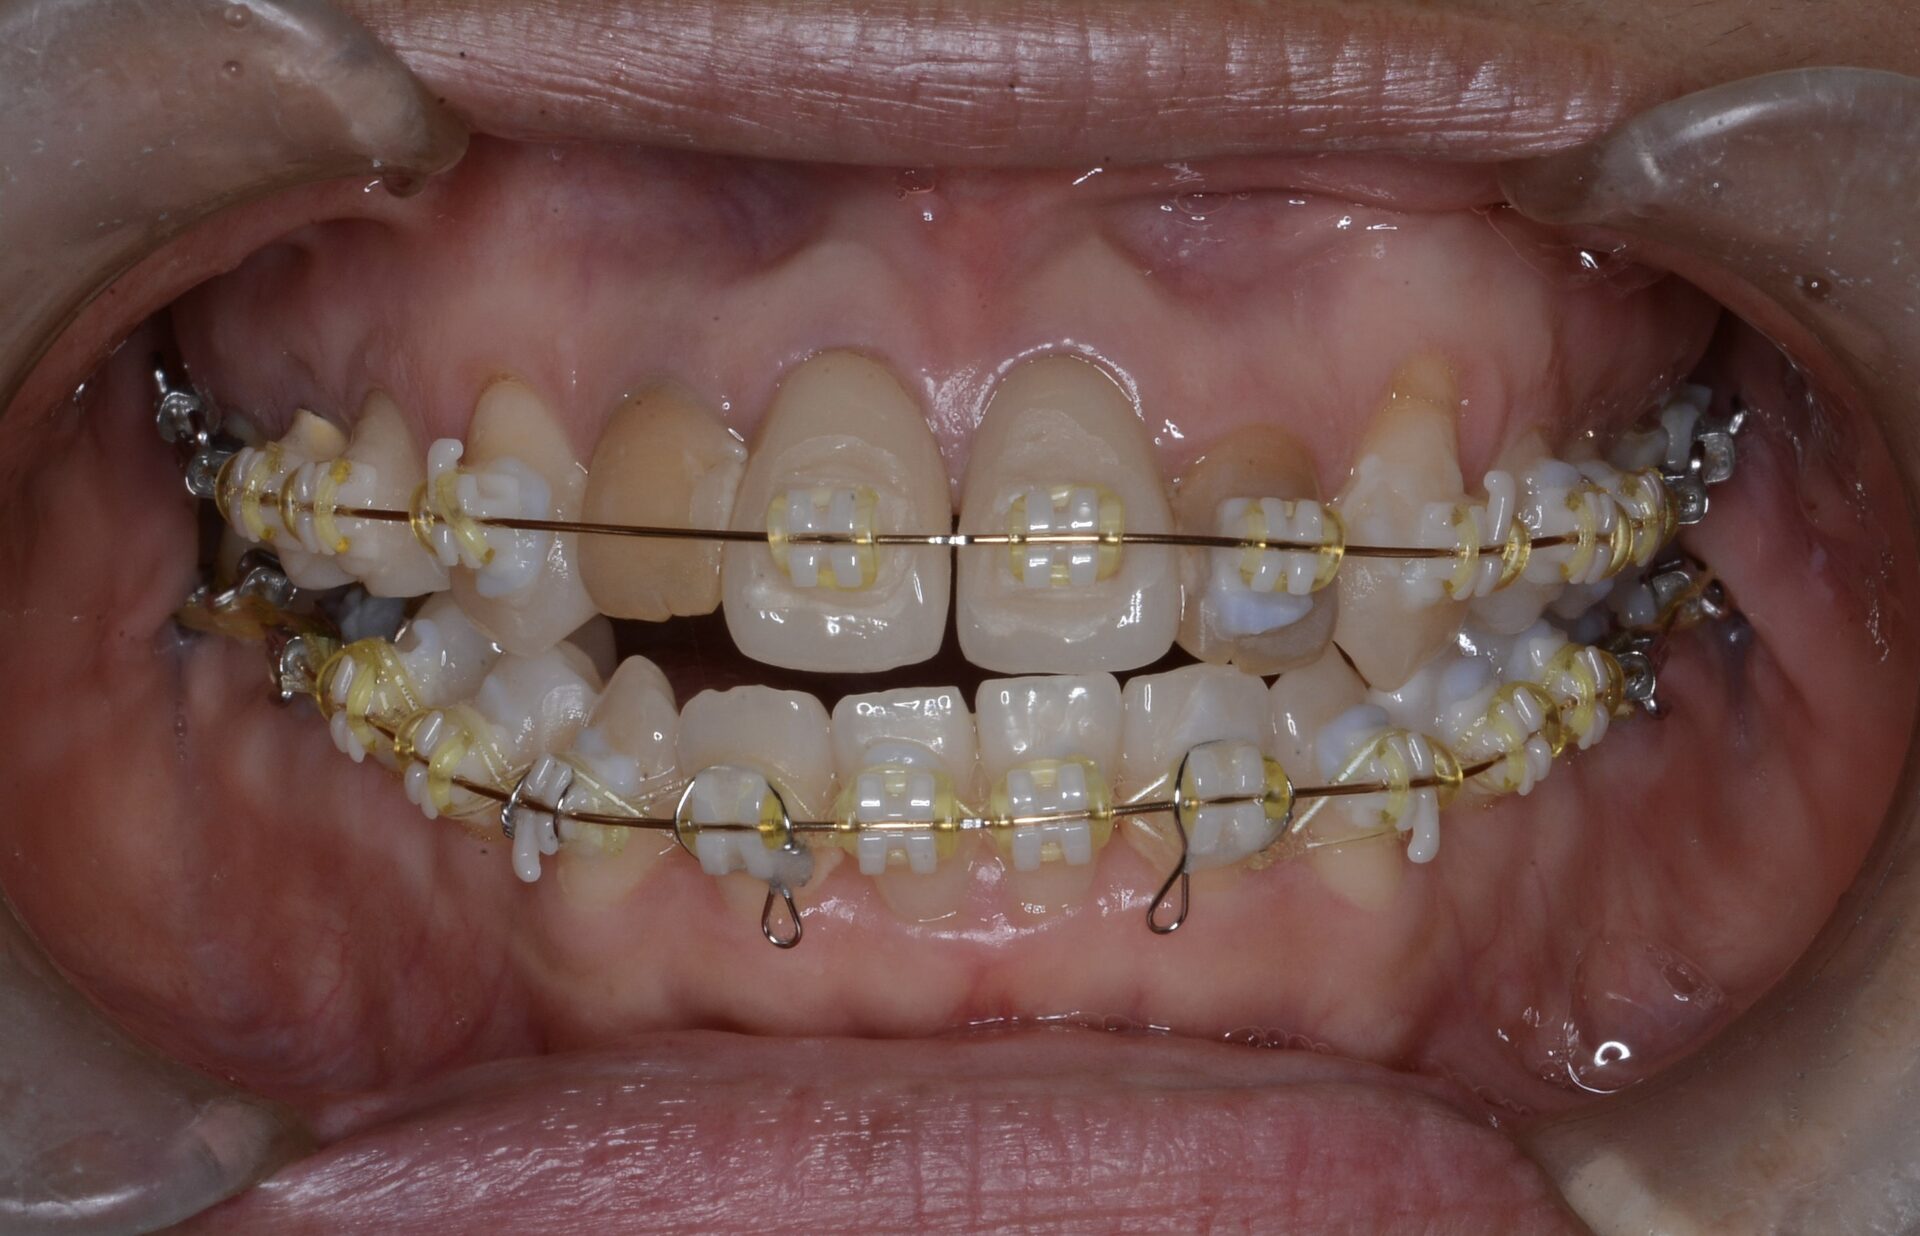

after

アンキローシスを起こしている側切歯を理想的な形の仮歯に置き換え、それを周りの歯を動かしより下顎と咬合させるためのアンカーとして利用した。

CT画像より親知らずが下歯槽管神経から十分離れたことを確認して抜歯を行う。

矯正治療中に意図した方向に歯が動かなかったり、時間がかかったりした場合に、あるどこかの歯が骨と癒着して全体の歯の動きを妨げていることがある。レントゲンで最初から見極めるのは私では困難で、ある程度矯正治療が進んできて初めてなんかおかしいと気がつくことが多い。。予定していたより時間がかかってしまい、患者さんにも負担をかけてしまった。歯の治療は患者さんの忍耐の上に成り立っていることを改めて感じた。今後ともメインテナンスでケアしていきますのでどうぞよろしくお願いします。